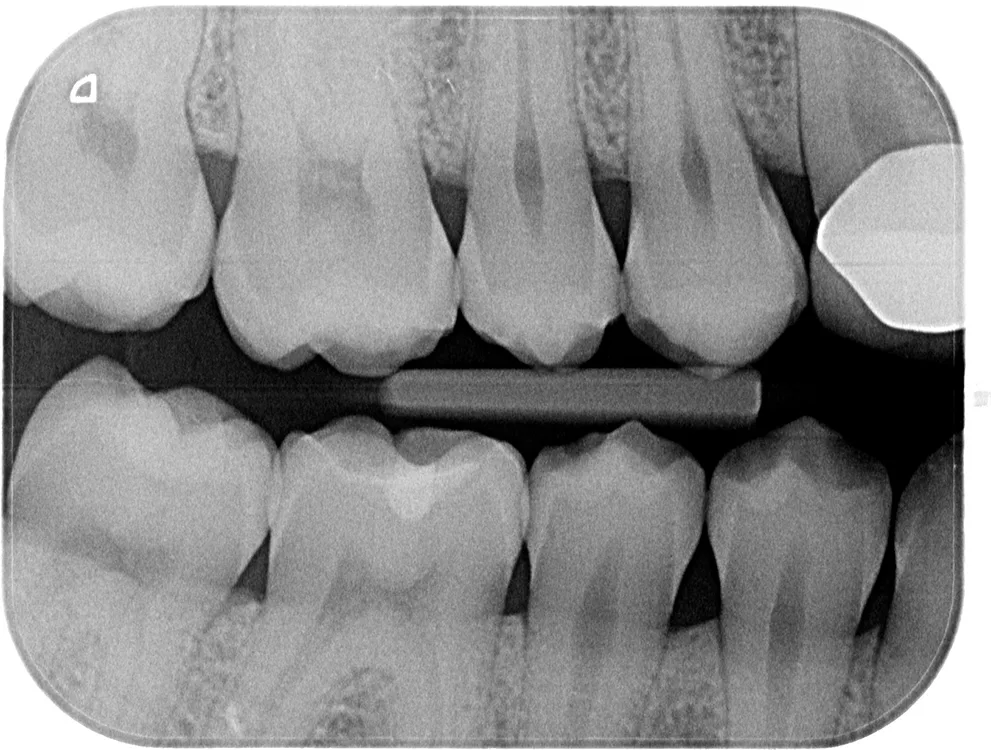

Röntgenologischer Befund

Das OPT (Abb. 1a) gibt keinen Anhalt auf nicht zahnverursachte Prozesse, alle vier Weisheitszähne sind vorhanden und retiniert. Die Bissflügelaufnahmen (Abb. 1b und c) zeigen insuffiziente konservierende Versorgungen an den Zähnen 26, 36, 37 und 46 sowie okklusale Karies an Zahn 16.